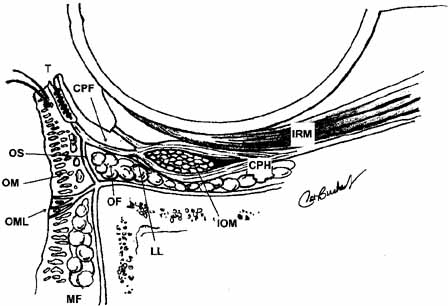

Lockwood20 described a hammock-like structure extending from the lateral orbital

tubercle to the medial canthal tendon comprised of the fused fascia

of the inferior rectus and inferior oblique muscles. The retractor

complex of the lower eyelid is composed of aponeurotic expansions of

the inferior rectus. These expansions form the capsulopalpebral head, which

divides to extend anteriorly around the inferior oblique muscle

and then fuses into Lockwood's ligament in front of the inferior

oblique to form the capsulopalpebral fascia.21 This fascia connects Lockwood's ligament to the inferior fornix, to

the inferior border of the tarsus, and to the preseptal orbicularis

muscle and skin at the level of the lid crease (see Fig. 12). It also contains the adrenergic smooth muscle fibers of the inferior

tarsal muscle, which are more diffusely distributed than in Müller's

muscle and do not insert directly onto the tarsus. Lockwood's

suspensory ligament is strongest immediately anterior to the

inferior oblique muscle and may help support the globe after removal

of the orbital floor. However, globe ptosis can occur after orbital

decompression for thyroid eye disease.  Fig. 12 Normal lower lid anatomy in cross section. (CPF, capsulopalpebral fascia; CPH, capsulopalpebral head; IOM, inferior oblique muscle; IRM, inferior rectus muscle; LL, Lockwood's ligament; MF, malar fat; OF, orbital fat; OM, orbicularis muscle; OML, orbitomalar ligament; OS, orbital septum; T, tarsus) Fig. 12 Normal lower lid anatomy in cross section. (CPF, capsulopalpebral fascia; CPH, capsulopalpebral head; IOM, inferior oblique muscle; IRM, inferior rectus muscle; LL, Lockwood's ligament; MF, malar fat; OF, orbital fat; OM, orbicularis muscle; OML, orbitomalar ligament; OS, orbital septum; T, tarsus)

|